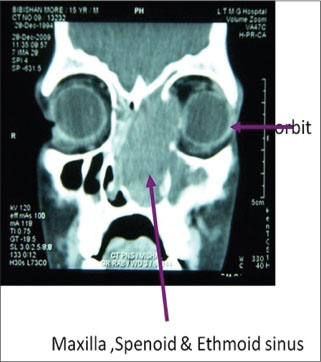

A 14-year-old male child presented with left side nasal obstruction for 3 months with epistaxis, 3?4 episodes. CT skull and nasal cavity showed soft-tissue lesion involving left nasal cavity extending into maxilla, sphenoid and ethmoid sinus, and sparing left orbit. Resection of the mass was done [Figure 7].

|?Figure. 7? A CT skull and nasal cavity shows soft-tissue lesion involving left nasal cavity extending into maxilla, sphenoid, and ethmoid sinus, sparing left orbit - c/o Plasmablastic lymphoma